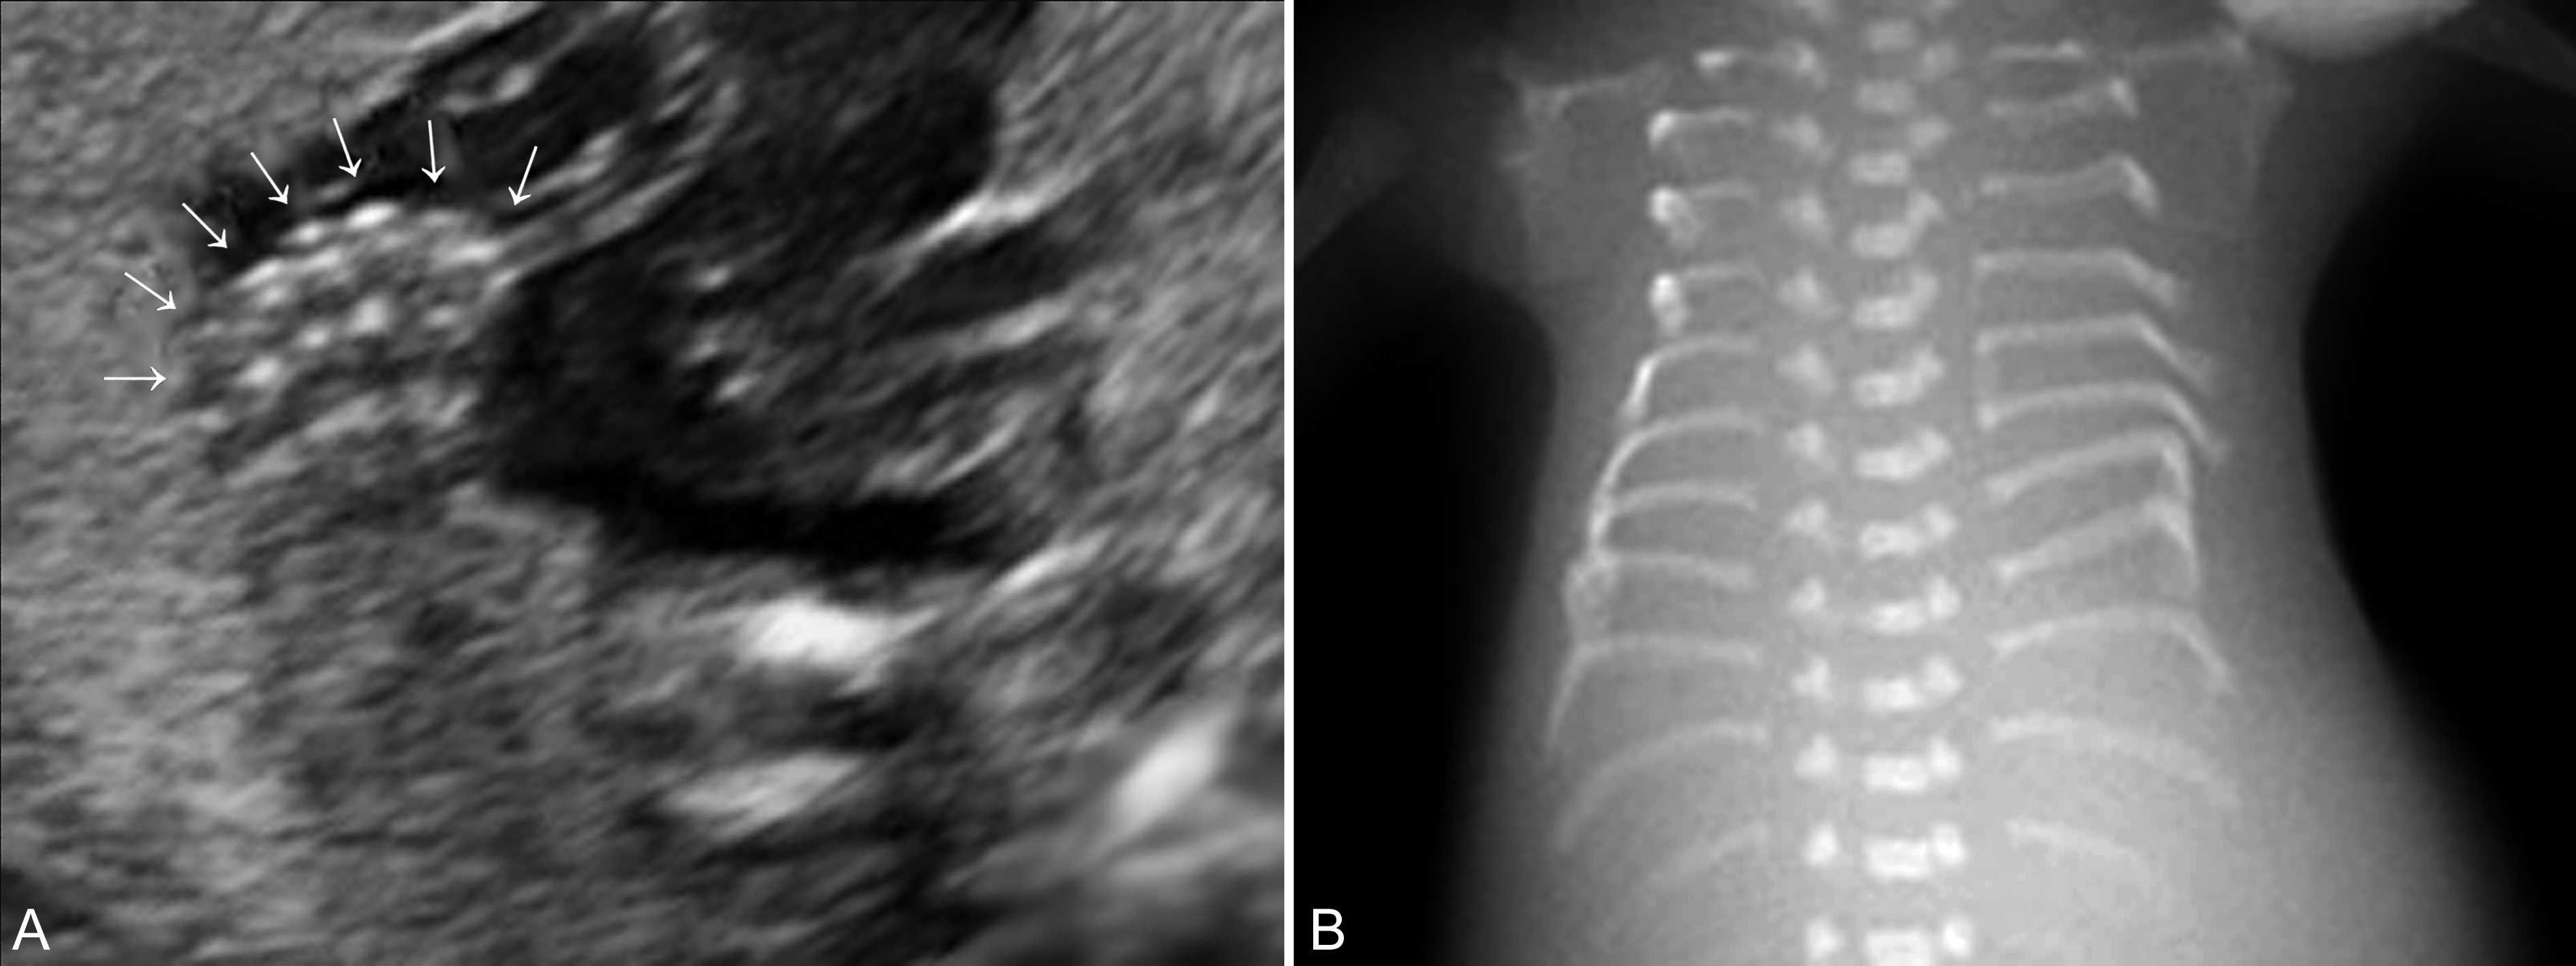

手(足)指(趾)的侧方的重复畸形,包括轴前型和轴后型多指(趾)畸形时,手(足)指(趾)的正常形态多可显示,仅仅是在手的一侧显示额外的回声,多数结构异常或骨骼短小,与正常的手指排列关系明显不一致,较短,指(趾)骨缩短或有弯曲,与相邻指(趾)骨或掌(跖)骨成角畸形(图3,图4)。如果不能显示手(足)指(趾)的正常形态并且指(趾)数增多,则为中央型多指(趾)畸形。显示中央型多指(趾)畸形时需要注意观察多指(趾)与邻指(趾)的关系,如果表面皮肤及皮下软组织完整,则为多指(趾)并指(趾)畸形。产前超声检查发现多指畸形后要注意胎儿头部、胸部、心脏及腹部的检查(图5),发现有无合并的畸形对预后的评估非常重要。

图5多指(A)-短肋(B)综合征畸形